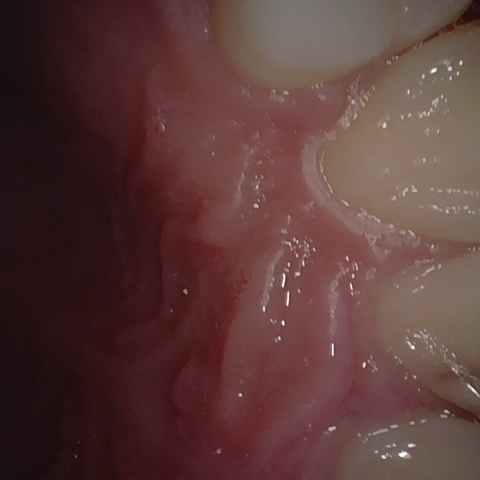

Annotated as "Good"